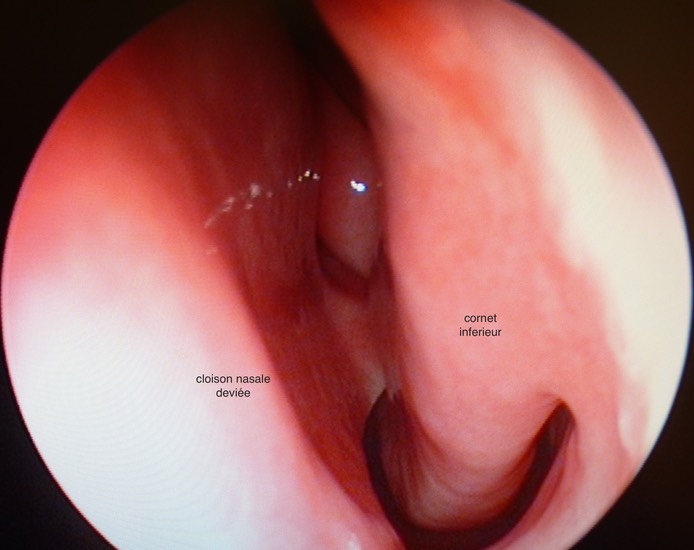

deviation cloison